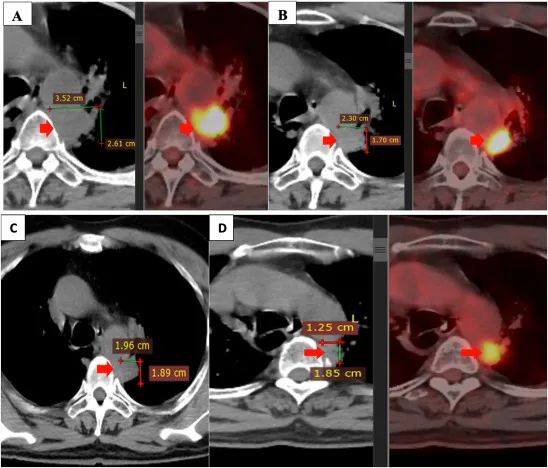

注:聯(lián)合治療前后的原發(fā)性腫瘤。原發(fā)腫瘤在二線治療(4 個(gè)周期的 alimta,卡鉑,可瑞達(dá))后進(jìn)展(A)。原發(fā)腫瘤在治療結(jié)束時(shí)與自體 NK 細(xì)胞療法,吉西他濱,貝伐珠單抗(B),3 個(gè)月后(C),6 個(gè)月(D)組合減少。

患者在 4 至 5 個(gè)月內(nèi)、每 3 周內(nèi)和在此期間每 3 周接受 6 個(gè)療程的自體 NK 細(xì)胞輸注。在此期間,患者在第 1 天和第 8 天(每 3 周 2 個(gè)周期)接受阿瓦斯汀(400mg,每 3 周 2 個(gè)周期)聯(lián)合吉西他濱(1800mg)治療,干咳和胸痛癥狀消失。患者飲食良好,生活質(zhì)量顯著提高。聯(lián)合治療期間未觀察到明顯副作用,肝腎功能評(píng)估在正常范圍內(nèi)。

2021 年 3 月和 2021 年 9 月進(jìn)行的 PET/CT 掃描顯示,與聯(lián)合治療前相比,原發(fā)腫瘤的大小顯著縮小。此外,兩側(cè)均未發(fā)現(xiàn)縱隔或鎖骨上淋巴結(jié)。